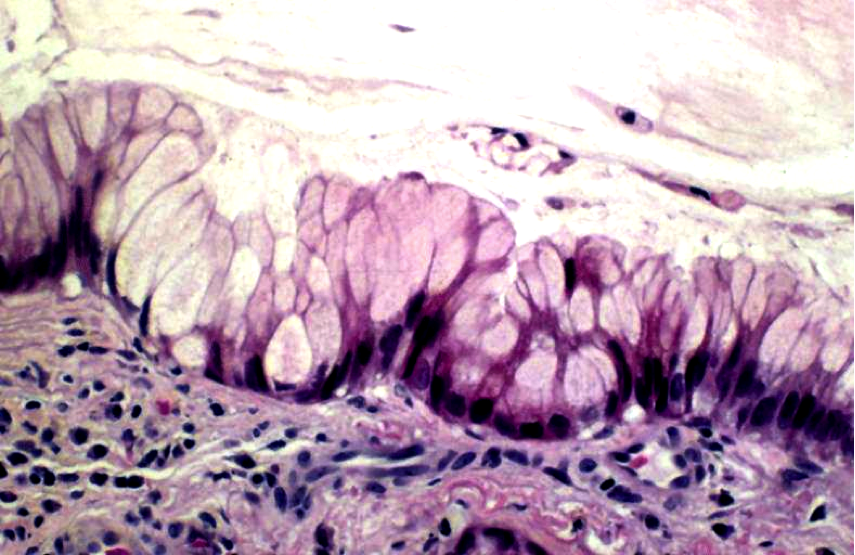

Colonic Hyperplastic Polyps:

Common

Benign but MUST be distinguished from Sessile Serrated Adenomas

When might you suspect Colonic Hyperplastic Polyps may actually be Sessile Serrated Adenomas?

Large (>1cm) in RIGHT colon